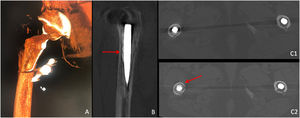

Femoroplasty technique. Image-guided monitoring. Patient aged 81 years. The fluoroscopic image shows that the vertebroplasty needle is located in the prosthetic stem area, with the bevel facing the area of interest. Different projections confirm the linear progression of the cement in the stem area during the cement injection (arrows).

Femoroplasty technique. Image-guided monitoring. Patient aged 80 years. The 3D image after rotational acquisition (Axiom Artis; vascular) (A) shows that the vertebroplasty needle is located in the prosthetic stem area. Confirmation that the cement is located around the stem (arrow; B). Comparative axial CT images at baseline (C1 image) and after femoroplasty (C2 image), showing the annular arrangement of the cement around the stem (arrow).